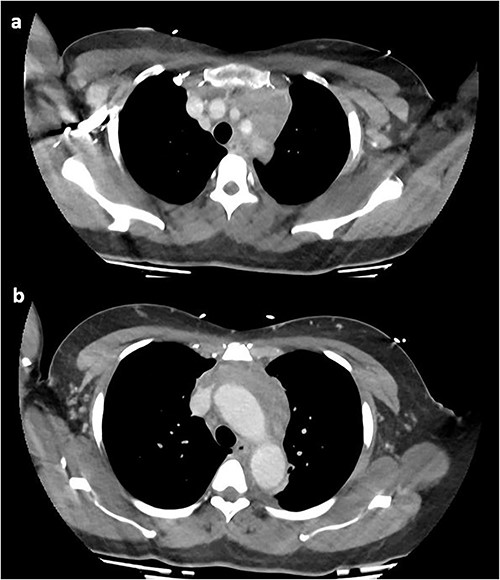

A computed tomography pulmonary angiogram (CTPA) was performed in the Emergency Department. Marked cresenteric aortic thickening from the level of the origin of the brachiocephalic trunk to the aortic hiatus in the diaphragm was noted, seen in Fig. 1. The CTPA was subsequently reported as an acute aortic intramural haematoma. The patient was transferred to the intensive care unit for blood pressure control with intravenous labetalol and cardiac monitoring.

On repeat review of the CTPA, imaging was deemed atypical for acute aortic syndrome. A CT aortogram with delayed phase was performed, which demonstrated a 66-mm upper anterior mediastinal soft tissue density compressing the left brachiocephalic vein, as seen in Fig. 2.

CT chest with contrast demonstrating anterior mediastinal soft tissue density in the (a) upper chest and (b) lower chest.